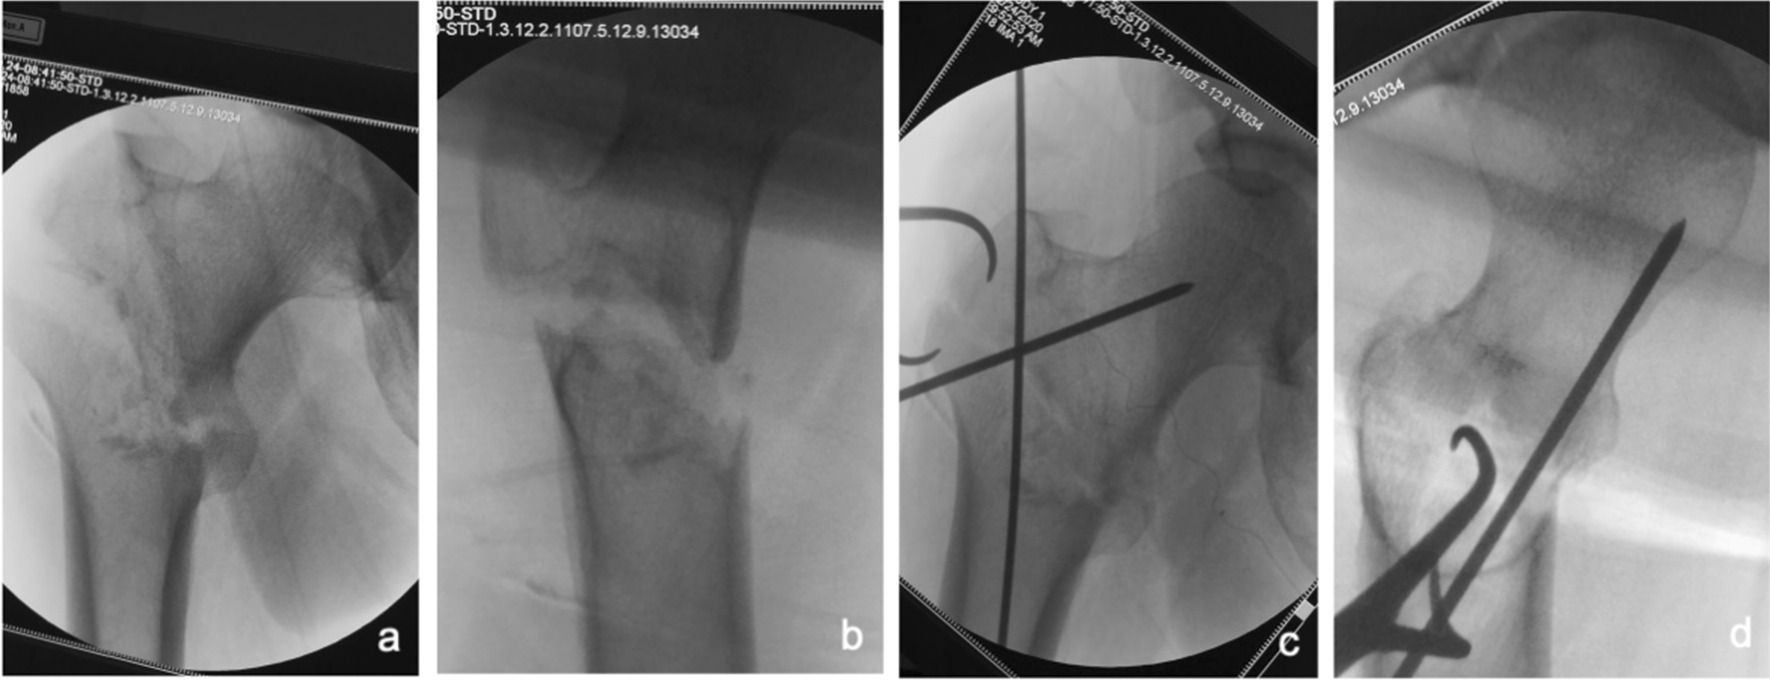

Fig. 3.

Anteroposterior and lateral X-ray films before and after reduction in patients with difficulty in reduction on the sagittal plane and pronation displacement of the proximal fracture segment a, b Before reduction; c, d After reduction (one head placed in front of the proximal fracture segment and the other head behind the greater trochanter)